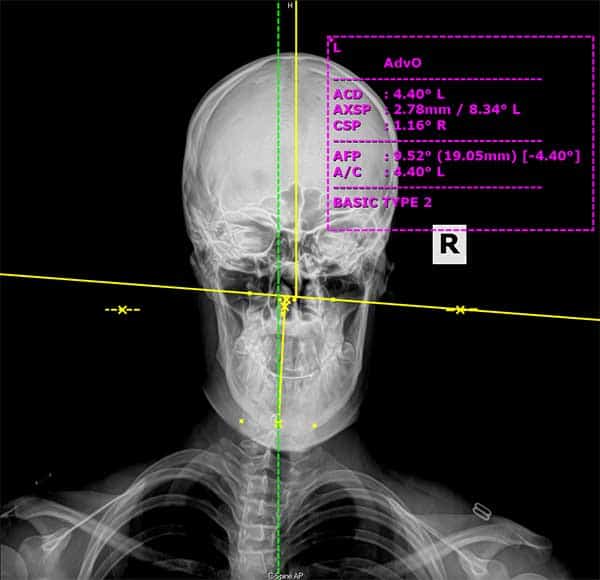

Traitement des Hautes Cervicales:

Ces techniques “de pointe” en Chiropractie ont été éprouvé dans les cas de vertiges chroniques par exemple. En effet, certains vertèbres très légèrement désaxées -comme l’Atlas ou l’Axis – sont parfois à l’origine de troubles graves tels que les vertiges ou autres dérèglement de l’oreille interne. Lisez mon article sur les techniques des Hautes Cervicales en Chiropractie pour plus de détail à ce sujet.